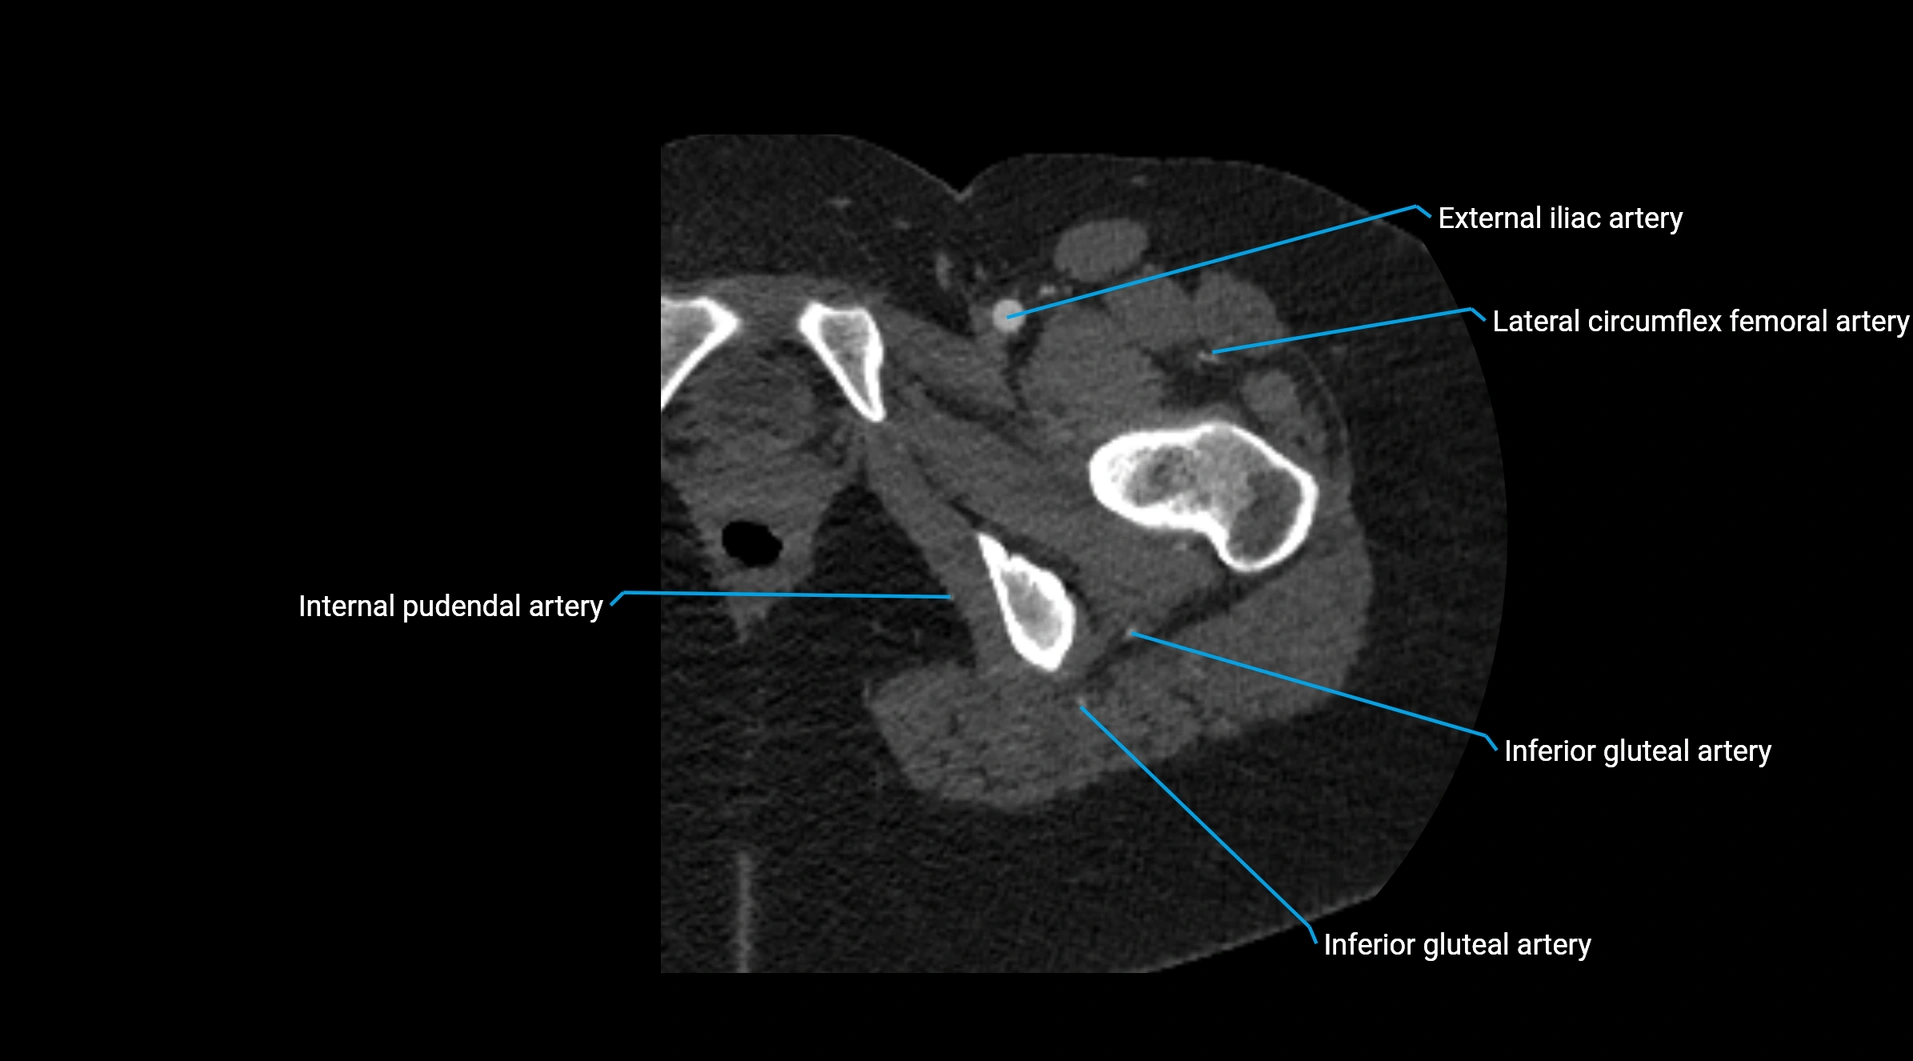

CT images

image

Contrast-enhanced CT (CTA):

• Gold standard for abdominal aortic imaging

• Provides excellent detail of lumen, wall, aneurysm, thrombus, and branch vessels

• Multiplanar and 3D reconstructions help in aneurysm measurement, stent graft planning, and dissection evaluation